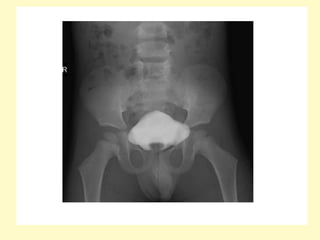

-Failure of the pubic bones to meet in the midline

(widened pubic symphysis), this appearance on AP plain

radiograph of the pelvis (manta ray sign)

3-Exstrophy : -There is2:1 predominance in males -Also known as ectopia vesicae, refers to a herniation of the urinary bladder through an anterior abdominal wall defect -Failure in development of the mesoderm below the umbilicus leads to absence of the lower abdominal and anterior bladder wall -Imaging findings include a soft-tissue mass extending from a large infra-umbilical anterior wall defect which may be close to the umbilical arterial exits, the absence of a normal urinary bladder and a low-lying umbilical cord insertion may also indicate the diagnosis -Failure of the pubic bones to meet in the midline (widened pubic symphysis), this appearance on AP plain radiograph of the pelvis (manta ray sign)